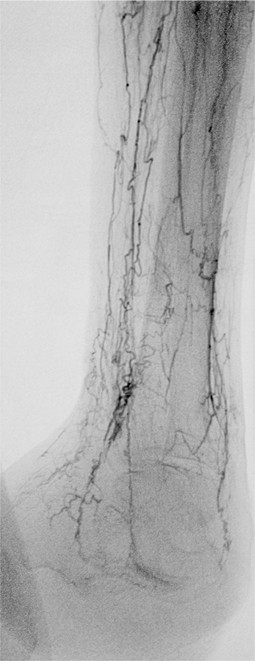

Deutsch Auch Morbus WiniwarterBuerger oder WiniwarterBuergerSyndrom Endangiitis obliterans Krankheit Medium hochladen Wikipedia Ist ein(e) Krankheit, designated intractable/rare diseases Unterklasse von arterial occlusive disease, predominantly mediumvessel vasculitis, secondary glomerular disease Benannt nach. Ischämie» die Differentialdiagnose eines Morbus WiniwarterBuerger erwogen Die selektive Angiographie vom zeigte die typischen «KorkenzieherKollateralen» am rechten Unterschenkel (Abb 1 x) Eine Ilomedintherapie war allerdings nicht erfolgreich, so dass am 1302 eine Grosszehenamputation rechts durchgeführt werden musste. Synonyme Morbus WiniwarterBuerger, VonWiniwarterBuergerKrankheit, Endarteriitis obliterans, Thrombangiitis obliterans Englisch endangitis obliterans, Buerger's disease Inhaltsverzeichnis.

Buerger related the cellular nature of arterial thrombosis, as had von Winiwarter, and described the absence of large vessel involvement It was Buerger who named the disorder “thromboangiitis obliterans”, and only briefly mentioned its relationship with smoking In 1924, Buerger reported that tobacco use was probably a predisposing factor 2. Morbus WiniwarterBuerger Stuttgart, Germany Georg Thieme;. Ischämie» die Differentialdiagnose eines Morbus WiniwarterBuerger erwogen Die selektive Angiographie vom zeigte die typischen «KorkenzieherKollateralen» am rechten Unterschenkel (Abb 1 x) Eine Ilomedintherapie war allerdings nicht erfolgreich, so dass am 1302 eine Grosszehenamputation rechts durchgeführt werden musste.